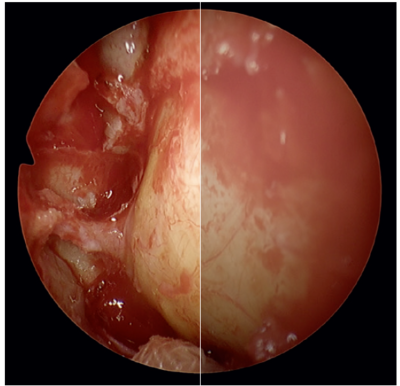

Magnified Visualization

Get Closer

- Panoramic view for the whole OR team with optimal viewing distance and wide viewing angle

- Structure enhancement processing based on image enhancement technology enables clearer recognition of human tissue and instruments in the body cavity

- Allows surgeons to observe fine patterns and structures of tissues in the body in high precision even when enlarged

- Equivalent to Full HD resolution even at 2.0x zoom

- Electric zoom allows for the scope to be moved from the operating field in order to avoid mist and smoke and to reduce "sword-fighting" of hand instruments